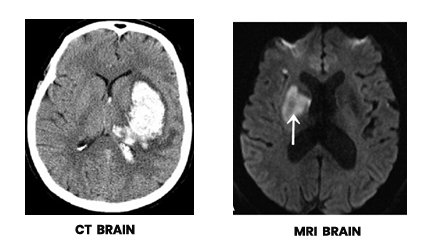

HOW DOES THE DOCTOR DIAGNOSE A STROKE?

The doctor confirms that a person has stroke by taking a detailed medical history of the person, a physical examination, blood tests, and x-ray studies including Computed Tomography (CT), Magnetic Resonance Imaging (MRI), CV Doppler studies and angiography. This will help to determine the type and location of the stroke and why the stroke happened.